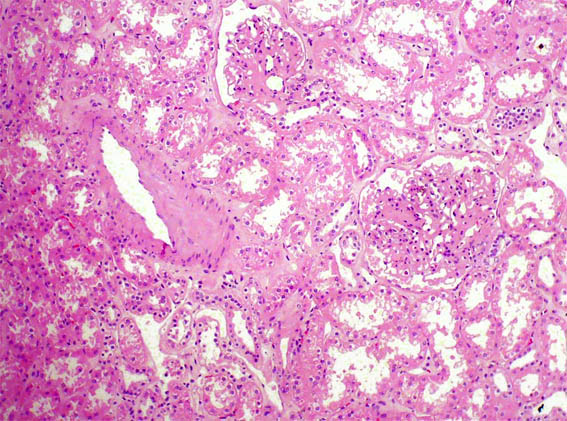

Figura 2.

H&E, X100.